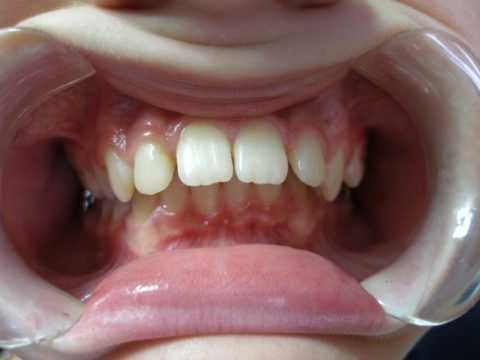

Симптомы мезиального прикуса

При мезиальном прикусе может отмечаться сочетание тех или иных лицевых и внутриротовых признаков, а также обусловленных ими различных функциональных нарушений. Внешне мезиальный прикус проявляется выдвижением подбородка и нижней губы вперед, западением верхней губы, нередко - зиянием ротовой щели. При этом средняя треть лица в профиль выглядит запавшей, вогнутой. В целом выражение лица пациента с мезиальным прикусом характеризуется как «сердитое».

Внутриротовые признаки мезиального прикуса характеризуются обратным резцовым перекрытием или прямой окклюзией зубов в переднем отделе; наличием мезиальной ступеньки при смыкании жевательных зубов. Возможен оральный наклон зубов на нижней челюсти, образование диастем и трем, наличие дистопированных зубов. Скученное положение зубов на нижней челюсти может обусловливать отложение зубного камня, развитие гингивита и пришеечного кариеса.

Основные внешне определяемые признаки дистального прикуса:

- выпуклое лицо в профиль;

- значительно выдвинутая верхняя челюсть, при одновременном сильно сдвинутом назад подбородке;

- невозможность сомкнуть губы в состоянии покоя;

- губа верхней челюсти зачастую оттопырена и не закрывает зубы, нижняя располагается позади верхних резцов.

У больного могут отмечаться расстройства в выполнении функций жевания, глотания и артикуляции. Внешние признаки патологии могут быть одинаковы при разных формах дистальной окклюзии.

Лицевые признаки дизокклюзии вызывают эстетическую неудовлетворенность. В полости рта больные отмечают в основном только глубокое перекрытие зубами верхней челюсти нижней.